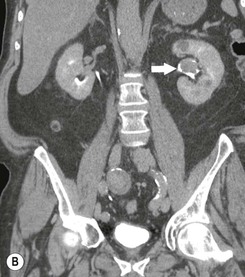

Μέθοδο εκλογής στη διάγνωση της νόσου αποτελεί η αξονική πυελογραφία με πολύ υψηλή ευαισθησία και ειδικότητα. Είναι πολύ σημαντικό να διενεργείται και κυστεοσκόπηση για τον αποκλεισμό συνυπάρχουσας βλάβης στην ουροδόχο κύστη. Η κυτταρολογική ούρων έχει θέση ως συμπληρωματική εξέταση κατά τη διερεύνηση της μικροσκοπικής αιματουρίας, παρότι το αρνητικό αποτέλεσμα έχει χαμηλή διαγνωστική αξία.

Οι ασθενείς στους οποίους ανευρίσκεται έλλειμμα σκιαγράφησης στην αξονική πυελογραφία πρέπει να υποβάλλονται σε διαγνωστική ουρητηροσκόπηση και λήψη υλικού προς βιοψία από τις ύποπτες περιοχές ώστε να γίνει σωστή σταδιοποίηση και βέλτιστη αντιμετώπιση της νόσου.